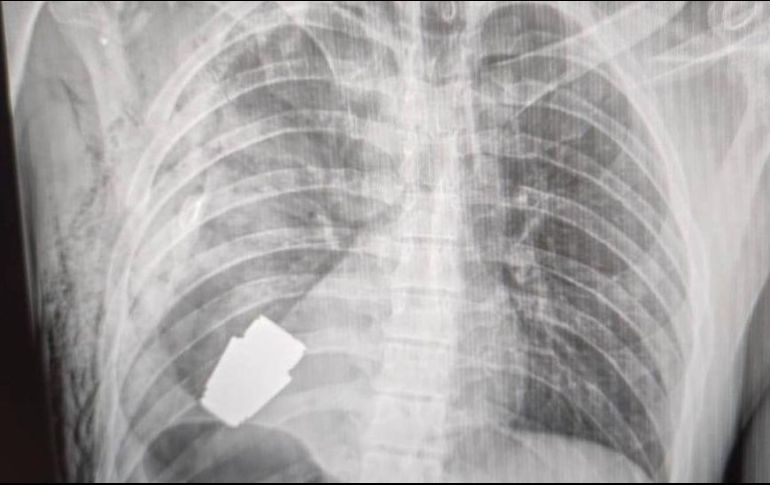

Ucrania (Marcrix Noticias).- El gobierno ucraniano describió como un “susto afortunado” la terrible experiencia por la que tuvo que pasar un soldado herido, a quien le extrajeron con éxito una granada que se encontraba en su pecho.

El cirujano Andriy Verba muestra la granada después de la operación. Hanna Maliar Facebook

Durante la operación no se pudo utilizar la electrocoagulación, procedimiento común en las cirugías del corazón para evitar que el paciente sufra una hemorragia, por temor a que la corriente eléctrica pudiera detonar la granada.

El fragmento de la granada de fabricación rusa que quedó alojado en el cuerpo del soldado tenía cuatro centímetros de diámetro y pesaba 275 gramos.